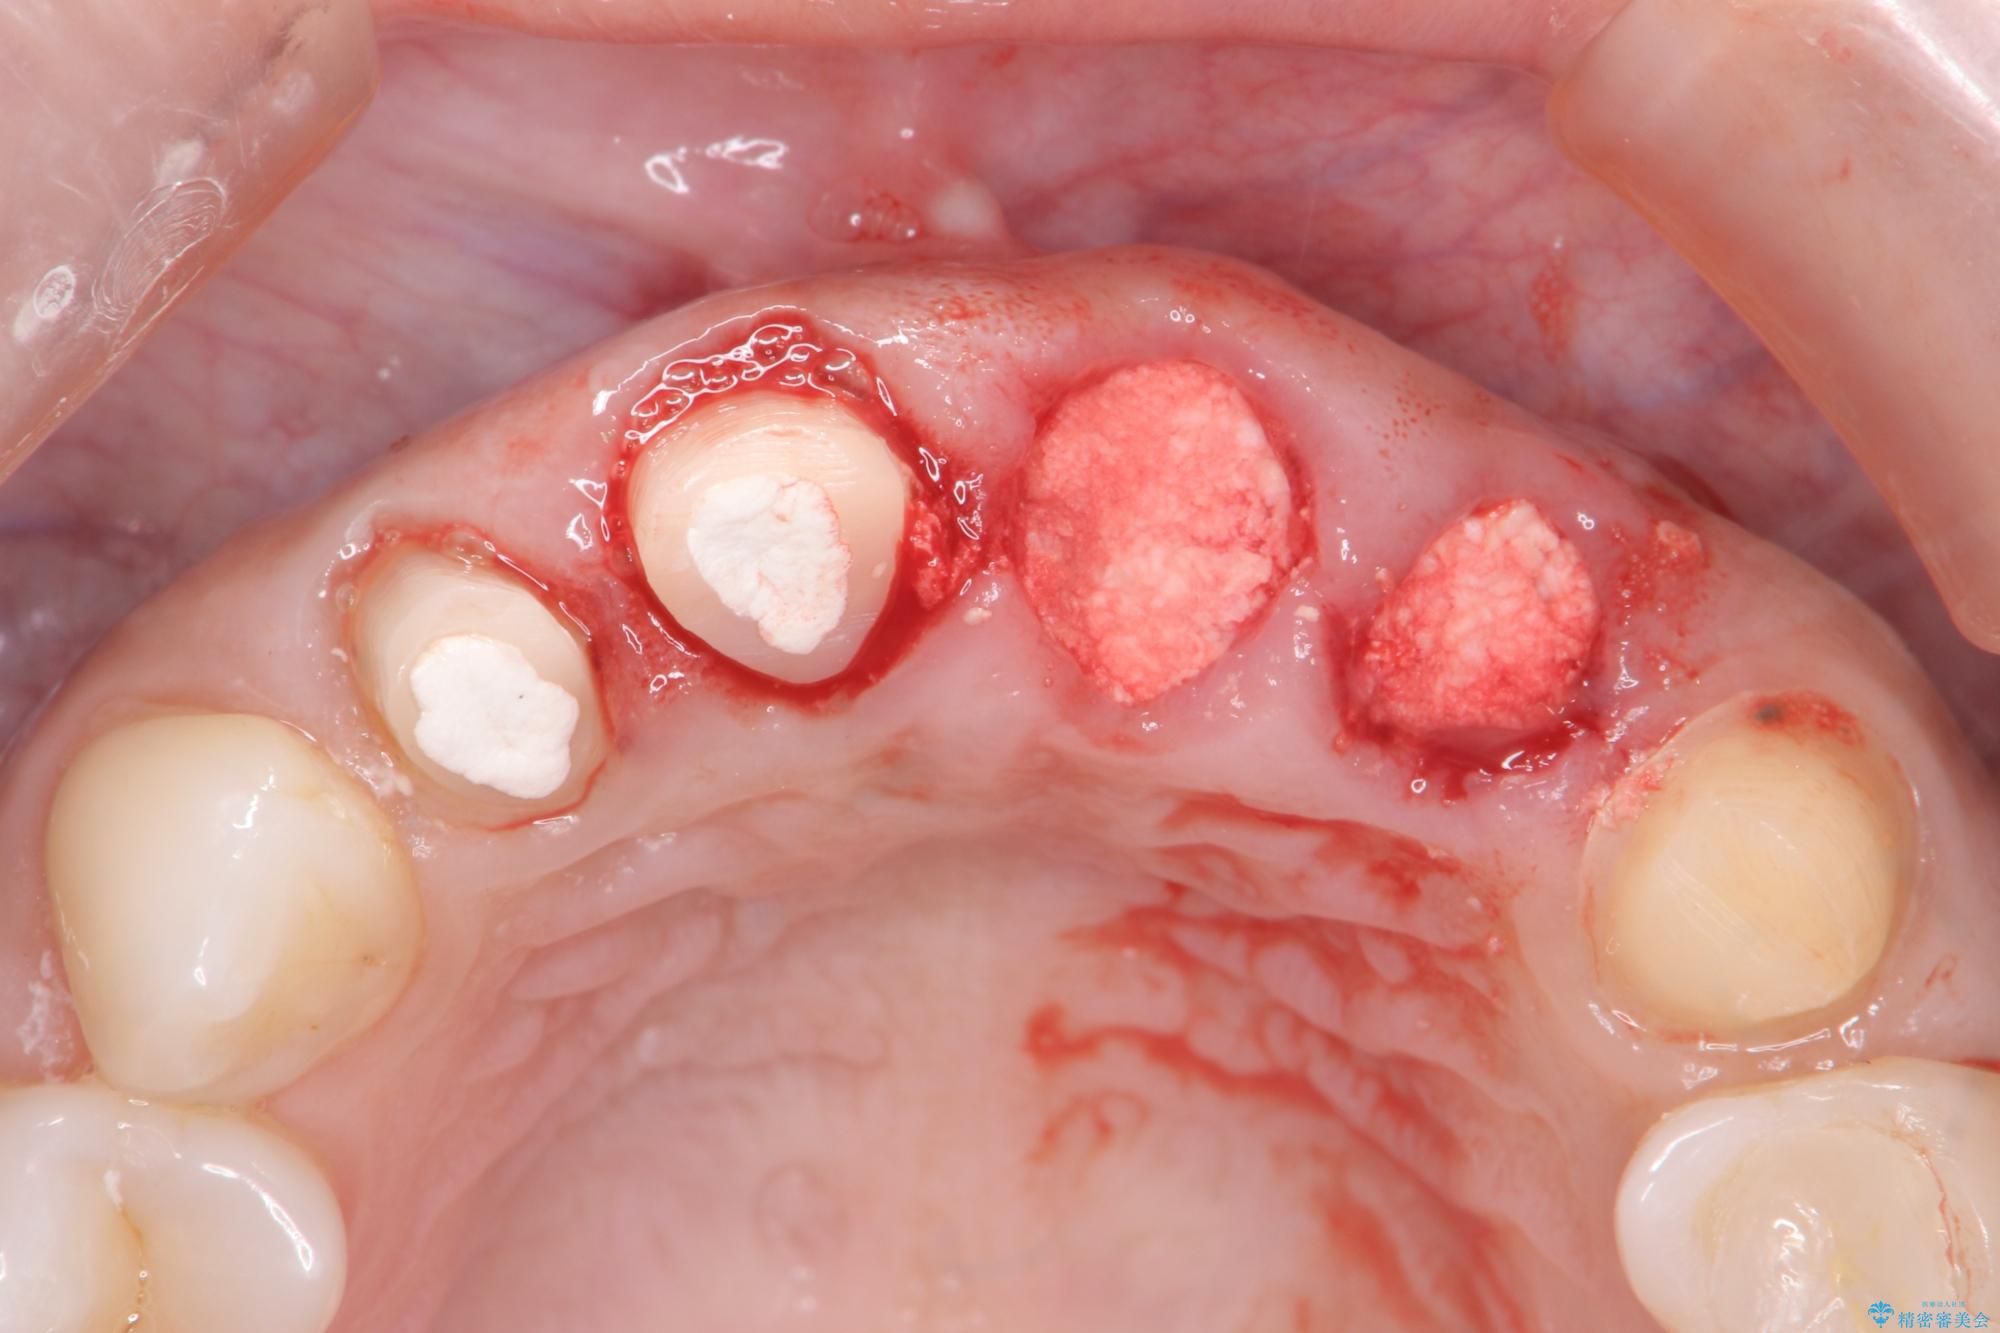

抜歯時に可及的に歯肉のボリュームを保つよう骨充填材とコラーゲン製剤による填塞を行い審美的かつ機能的なブリッジとなるよう治療を進めます。

治療中

歯槽堤保存術を併用したブリッジ治療 治療中画像 歯槽堤保存術を併用したブリッジ治療 治療中画像 歯槽堤保存術を併用したブリッジ治療 治療中画像 歯槽堤保存術を併用したブリッジ治療 治療中画像 歯槽堤保存術を併用したブリッジ治療 治療中画像 歯槽堤保存術を併用したブリッジ治療 治療中画像 歯槽堤保存術を併用したブリッジ治療 治療中画像